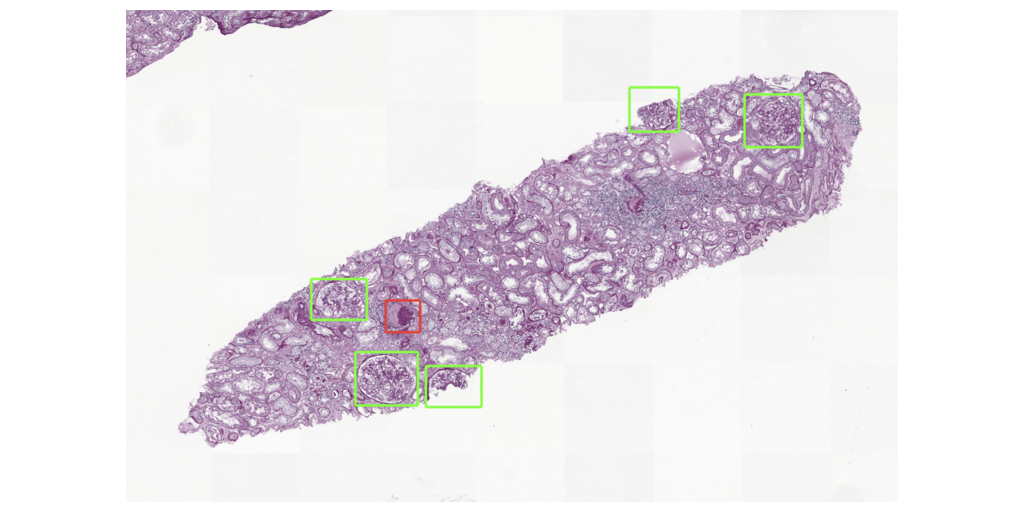

NIJMEGEN, Pays-Bas–(BUSINESS WIRE)–Aiosyn, éditeur de logiciels médicaux spécialisé dans les solutions liées à la pathologie et alimentées par l’IA, a annoncé la sortie d’une suite rénale d’IA conçue pour faire avancer la recherche dans le domaine des maladies rénales. S’appuyant sur une technologie de pointe d’apprentissage approfondi, cette solution innovante fournit aux entreprises biopharmaceutiques et de recherche des outils puissants pour analyser les structures rénales et quantifier les lésions qui ont un impact sur la santé rénale. La suite rénale d’IA d’Aiosyn marque une nouvelle étape importante pour l’entreprise, qui fait suite au récent lancement d’Aiosyn Mitosis Research.

Avec 850 millions de personnes dans le monde entier souffrant de maladies rénales (1) et l’insuffisance rénale chronique (IRC) qui devrait devenir la cinquième cause de décès d’ici 2040(2), il existe un besoin urgent d’améliorer le diagnostic et le traitement. La suite rénale d’IA d’Aiosyn utilise des algorithmes de pathologie computationnelle alimentés par l’IA pour quantifier objectivement les scores des lésions rénales, offrant ainsi la possibilité d’améliorer la reproductibilité et d’accélérer le développement de médicaments. La plateforme résout le problème des limites de la classification de Banff actuellement utilisée dans l’analyse des biopsies rénales, qui subit la variabilité des observateurs et repose sur des évaluations qualitatives.

La suite rénale d’IA d’Aiosyn facilite l’identification et la caractérisation des processus pathologiques, et ouvre une voie prometteuse à d’importantes améliorations dans la recherche et les essais cliniques sur l’insuffisance rénale chronique. Parallèlement à sa plateforme d’IA rénale, Aiosyn développe activement des algorithmes avancés d’apprentissage approfondi visant à la détection de biomarqueurs du cancer.